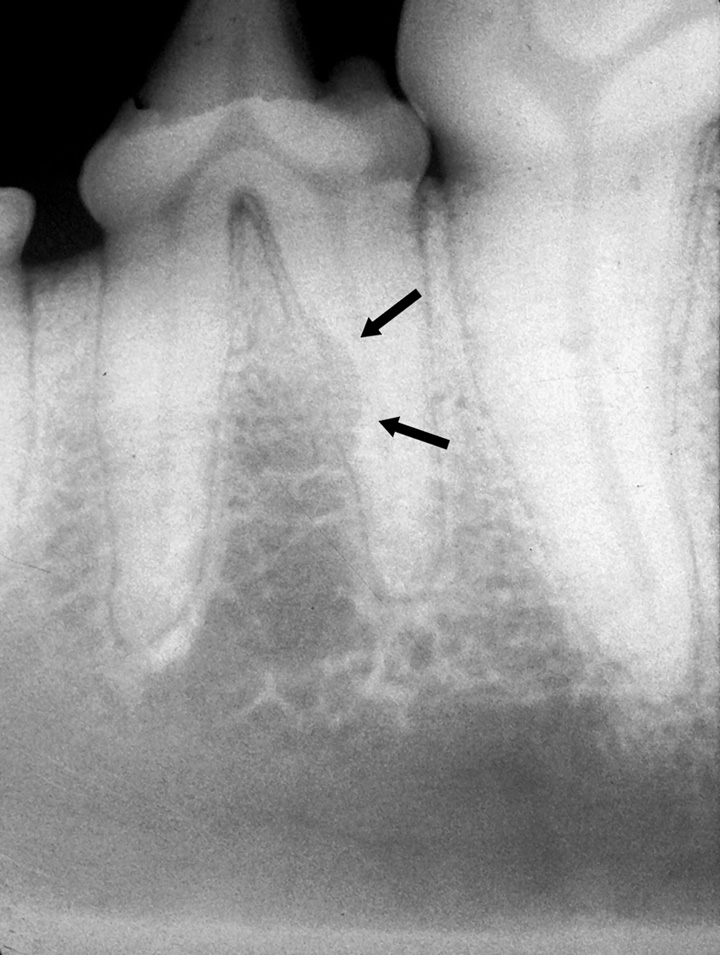

Tooth resorption. A/B) Clinical photograph and radiograph of maxillary Tooth Resorption Dog Treatment — the 2 most common types of tooth resorption were external replacement resorption (77/224 [34.4%] dogs and. — regular oral examinations with your veterinarian or veterinary dentist are essential for diagnosing tooth resorption. how is tooth resorption treated? — tooth resorption is a common dental finding in cats and dogs. — before we consider treatment. Tooth Resorption Dog Treatment.

Root Resorption due to delay in treating an impacted canine.... Dr Tooth Resorption Dog Treatment — tooth resorption is a common dental finding in cats and dogs. Dental radiographs help determine the extent and type of tooth. Provides an overview of the clinical indicators of root resorption. — how is tooth resorption treated? Its recognition and treatment are important to. — tooth resorption in dogs is a serious medical condition because it. Tooth Resorption Dog Treatment.

Tooth Resorption Animal Dental Specialist Tooth Resorption Dog Treatment while the first installment (january 2013 issue) outlined the various classifications of tooth resorption, the following segment maps treatment. Anatomically, the buccal surfaces of the mandibular premolars are most commonly affected. Dental radiographs help determine the extent and type of tooth. root canal therapy, an advanced procedure with guarded prognosis, can be used to treat cases of internal. Tooth Resorption Dog Treatment.